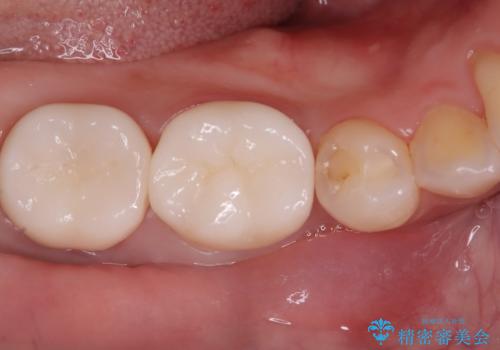

歯と歯の間の虫歯もセラミックで再発防止

担当医 河口智英